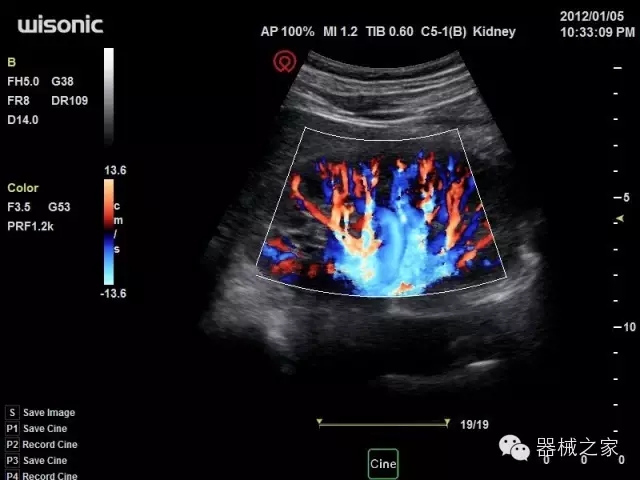

臨床圖片賞析